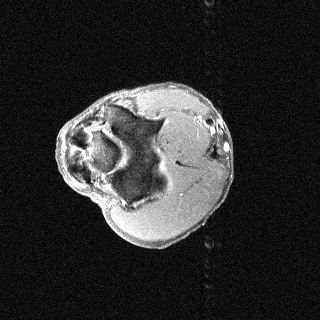

Orientation-specific examples grouped by anatomy. Select a category to view axial, coronal, and sagittal samples.

Axial

Axial sample